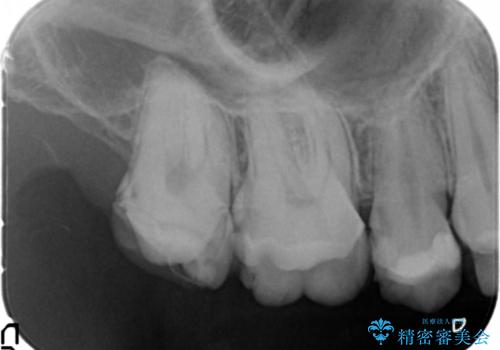

咬み合わせが悪く矯正も検討されていたそうですが、歯を真っ白にしたいというご希望もあり、28本のすべての歯をセラミックにしたいとのことでした。

精査したところ、ほとんどの歯が保険内のレジンで充填されており、咬み合わせも悪く咬合していない歯もありました。

虫歯をしっかりと治療したのち、オールセラミッククラウンによる補綴治療を行いました。

下顎の埋伏していた親知らずも抜去しました。